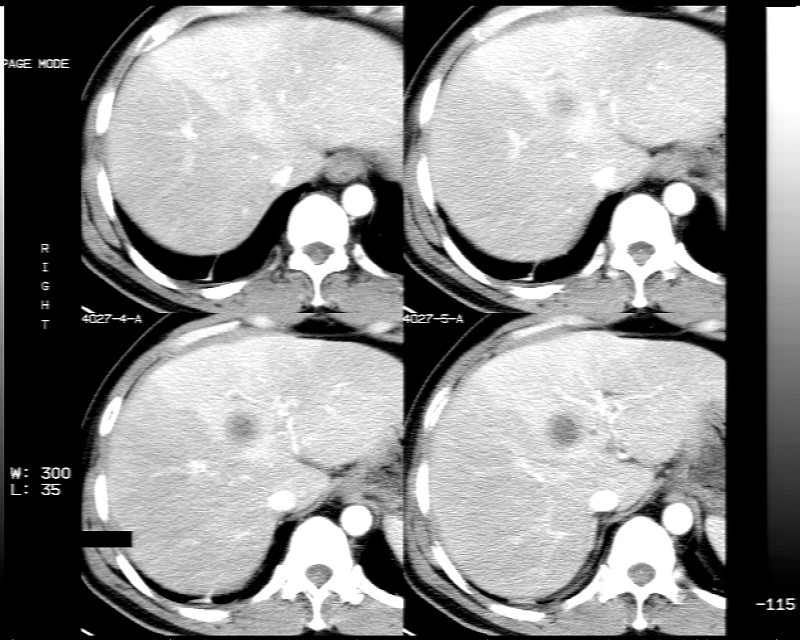

男性,52岁,腹痛,无发热,生化检查无明显异常,既往有胰腺炎病史,经治疗好转出院。

胆囊炎,肝脓肿(周围可见异常灌注)

1)考虑肝左叶内侧段肝脓肿,不排除转移瘤。2)脂肪肝。3)慢性胆囊炎。4)十二指肠降部肿瘤可能。

胆囊炎、脂肪肝、肝脓肿。